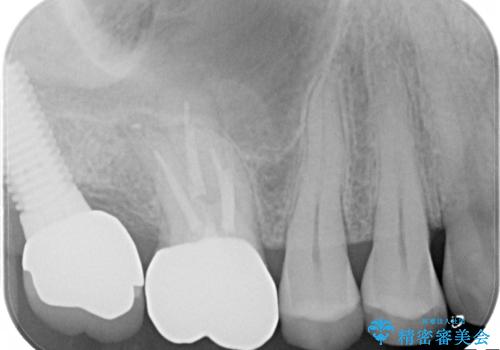

- 古い詰め物を除去し、腐ってしまった神経を顕微鏡下で丁寧に処理する

→根管治療完了後、土台を築造し、かぶせ物を製作してかみ合わせを回復する

すでに感染が根の先端まで及んでいたため、かなり強い痛みがありましたが、丁寧に根管治療をすることで内部を可及的に無菌化し、痛みが消失しました。

かぶせ物の種類:Bellezza